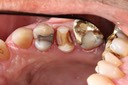

Matt Dodson #3 pre-op

Matt Dodson #3 caries removal